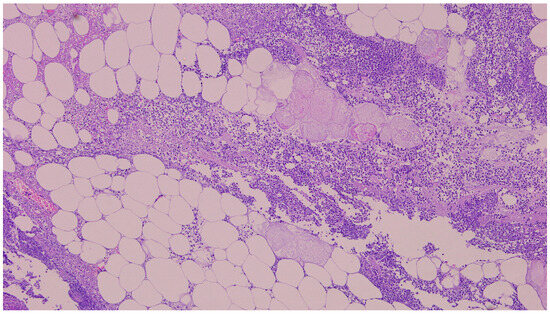

There were no signs of perforation of the hollow viscus organs, and the pancreas was observed to be normal. Resection of the RL was performed. The microbiological analysis of the biopsy sample revealed that Klebsiella varicola was susceptible to most antibiotics (MALDI-TOF MS, Bruker Corp., Billerica, MA, USA). The histopathological examination of the resected surgical specimen reveals a massive polymorphonuclear infiltration, diffuse steatonecrosis, and associated foamy histiocytes, as well as foci of fibrin and haemorrhage (Figure 2). The patient was treated with IV fluids, Piperacillin/Tazobactam, and PPI. She had an uneventful recovery and was discharged on the 5th postoperative day.

Figure 2. The histopathological examination of the resected surgical specimen (H&E) showed polymorphonuclear infiltration, steatonecrosis, fibrin, and foamy histiocytes (5×).